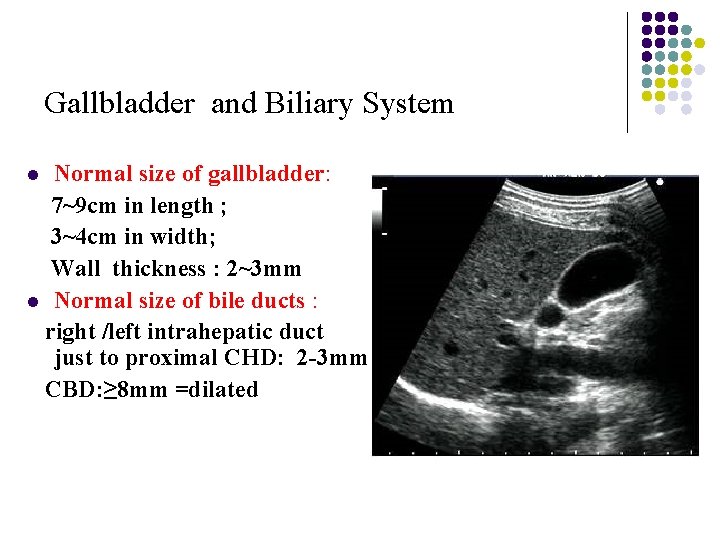

Gallbladder and Biliary System Normal size of gallbladder: 7~9 cm in length ; 3~4 cm in width; Wall thickness : 2~3 mm l Normal size of bile ducts : right /left intrahepatic duct just to proximal CHD: 2 -3 mm ; CBD: ≥ 8 mm =dilated l